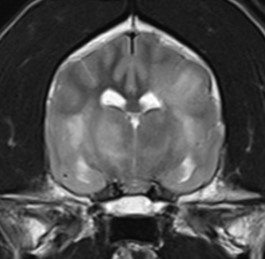

자기공명영상촬영 (MRI, Magnetic Resonance Imaging) 자기에너지를 이용하여 영상을 획득하기 때문에 방사선의 발생 없이 사람과 동물 모두에게 보다 안전한 영상 기법입니다.

MRI의 경우 특히 뇌와 척수의 신경계와 같은 연부조직의 영상화에 특화되어 있어 다른 영상 기법보다 뛰어난 해상도를 나타냅니다.

건국대학교 영상진단의학과에서는 1.5 Tesla의 최신 자기공명영상촬영장치를 통해 높은 수준의 해상도를 제공하고 추가적으로 환자에게 맞는 다양한 검사 sequence가 가능하여 보다 정밀한 진단을 위해 노력하고 있습니다.

- 뇌수두증

- 뇌종양

- 뇌수막염

- 두경접합부 질환

- 디스크 질환

- 척수 질환

뇌수두중 -

후두골이형성,키아리 기형 -

척수공동증 -

AAI